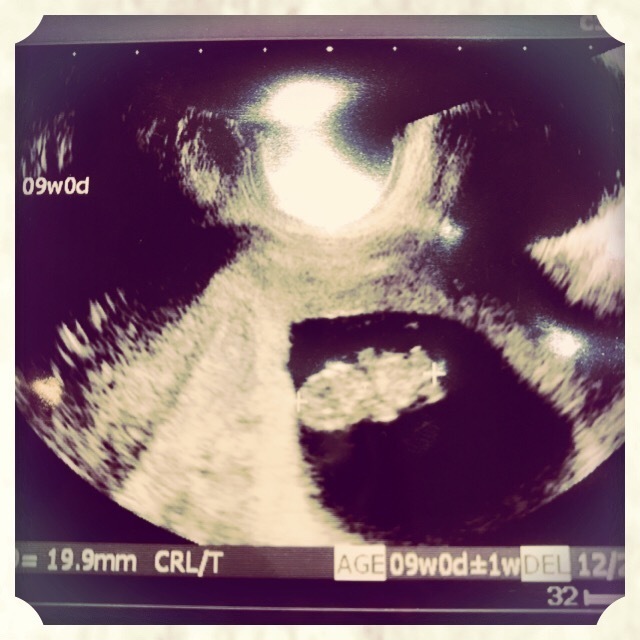

8週0日(8w0d・性別不明)|まなん(´ω`) さん(35歳)

エコー写真撮影時のエピソード:生活面ではニオイでの悪心増悪があり、食事も酸っぱいものを求めるようになったことや長男妊娠中と同じく強い立ちくらみもあり、妊娠かな?と受診したら8週目でした。絨毛膜下血腫があり、自然消失を待ってる状態です。胎児ちゃん自体はエコーで心拍も確認でき、元気な様子でした。このまま大きくなってねと祈りながらエコー映像を見てます。